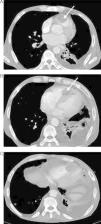

Para melhor caracterização e estadiamento da doença, realizou uma tomografia axial computorizada (TC) cérvico-tóraco-abdominal, que mostrou sinais de metastização difusa, envolvendo a região cervical, tecido pulmonar, hepático, suprarrenal e ósseo, para além de ter confirmado a presença da massa ventricular direita (Figura 3A-B). Verificou-se adicionalmente na dependência do pericárdio adjacente à parede lateral do ventrículo esquerdo uma outra massa (Figura 3C).